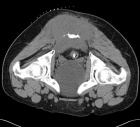

25 y/o male with chronic coccygeal pain who presents with progressive left buttock mass. Mild constipation. No other complaints. Smoker, otherwise healthy.

PE: Large, nontender mass involving L>R buttock with induration and erythema. Neurovascularly intact

Zoom image: Radiological image Radiological image.